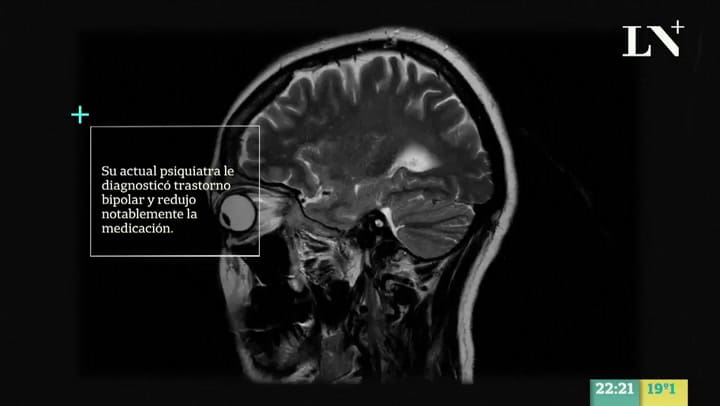

En Signos de los tiempos se expuso el caso de Verónica Mountford, una mujer que, luego de atravesar un divorcio, entró en crisis y le diagnosticaron depresión. A partir de allí su vida cambió completamente porque estuvo medicada durante diez años y sufrió serios cambios en su personalidad a raíz de un diagnóstico equivocado.

"Empecé a los 50 años con una crisis por mi divorcio, me diagnosticaron como depresiva, me daban somníferos. Tuve crisis de angustia, diez internaciones y ataques de pánico. Recién en el 2010 me dijeron que era bipolar y lo peor que se le puede dar a un paciente así es un antidepresivo", contó Mountford.